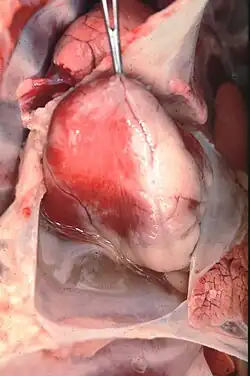

Heartwater (also known as cowdriosis, nintas, and ehrlichiosis) is a tick-borne rickettsial disease.[2] The name is derived from the fact that fluid can collect around the heart or in the lungs of infected animals.[3] It is caused by Ehrlichia ruminantium[4] (formerly Cowdria ruminantium)—an intracellular Gram-negative coccal bacterium (also referred to as Rickettsia ruminantium). The disease is spread by various Amblyomma ticks, and has a large economic impact on cattle production in affected areas. There are four documented manifestations of the disease. These are acute, peracute, subacute, and a mild form known as heartwater fever. There are reports of zoonotic infections of humans by E. ruminantium, similar to other Ehrlichia species, such as those that cause human ehrlichiosis.[5][6][7]

On post mortem examination, a light yellow transudate that coagulates on exposure to air is often found within the thorax, pericardium, and abdomen. Most fatal cases have the hydropericardium that gives the disease its common name. Pulmonary oedema and mucosal congestion are regularly seen along with frothy fluid in the airways and cut surfaces of the lungs. To definitively diagnose the disease, C. ruminantium must be demonstrated either in preparations of the hippocampus under Giemsa staining or by histopathology of brain or kidney.